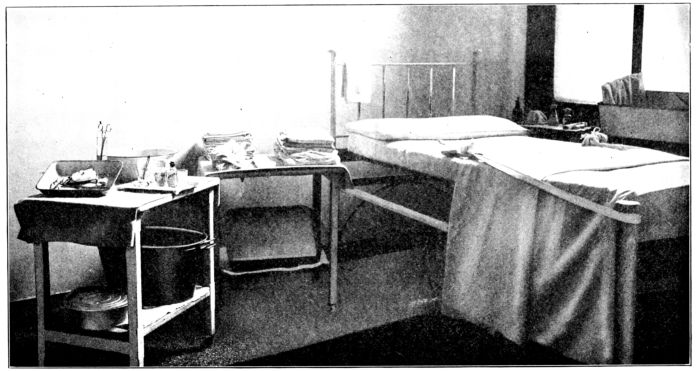

| 79. | Bed and simple equipment ready for normal delivery | 258 |

| 80. | Instruments shown in Fig. 79 | 260 |